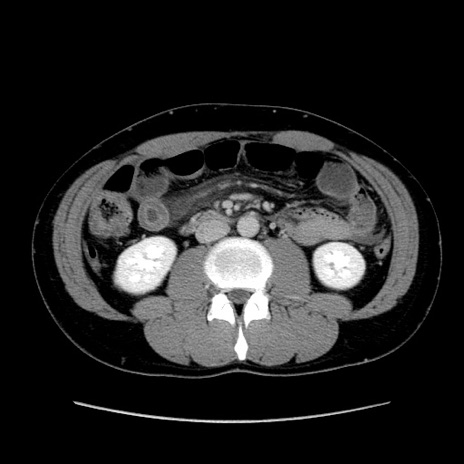

冠状断像

【症例】20歳代 男性

【主訴】心窩部痛

【現病歴】今朝より上腹部痛あり。一旦軽快していたが再度出現したため救急要請。昨日夕に白身の魚を含む刺身を食べた。

【身体所見】BP 136/89mmHg、HR 74/min、BT 37.0℃、腹部:膨満、軟、心窩部に圧痛あり。反跳痛なし、筋性防御なし、腸雑音やや亢進あり。

【データ】WBC 17700、CRP 0.48